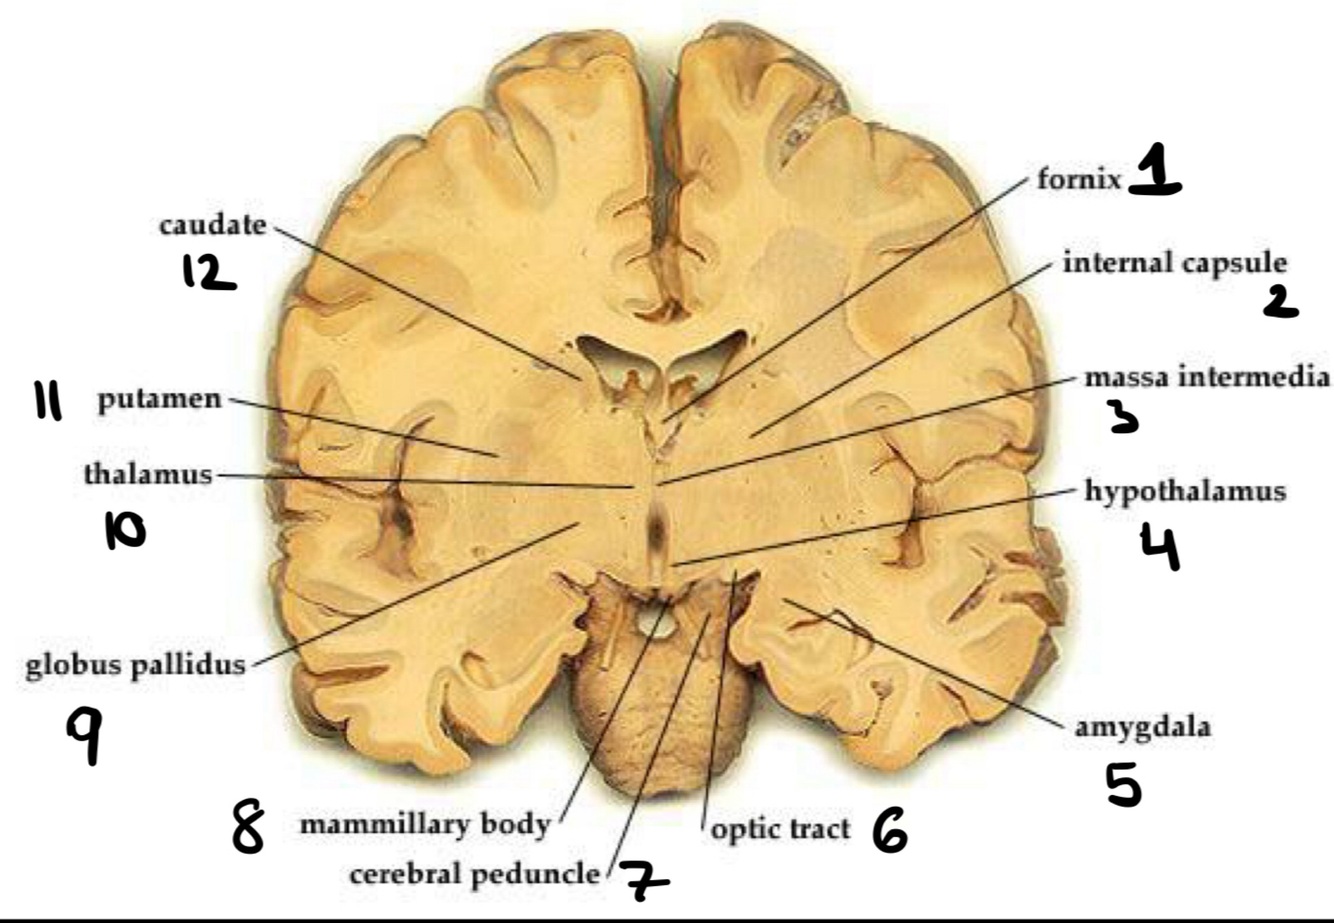

Name the structure

Hypophisis